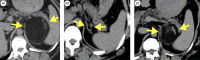

Case presentation: A 24-year-old male patient with Prader-Willi syndrome presented with an enlarged adrenal tumor. Computed tomography detected a well-defined mass. Magnetic resonance imaging revealed an increased signal intensity predominantly in fatty areas, suggesting adrenal myelolipoma. Laparoscopic left adrenalectomy was performed. Postoperatively, the patient developed mild pulmonary atelectasis, myelolipoma was confirmed by histopathology, and there was no recurrence at approximately 2 years postoperatively.